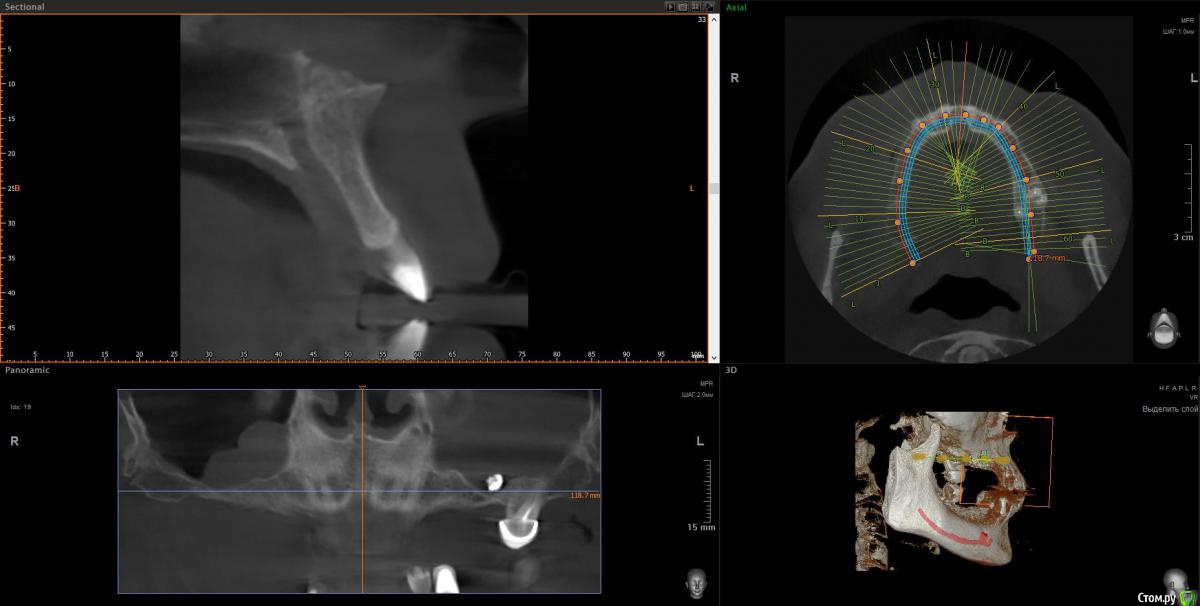

wladdX Опубликовано 9 апреля, 2018 Поделиться Опубликовано 9 апреля, 2018 Несколько скриншотов 2 Ссылка на комментарий

Irouil Опубликовано 10 апреля, 2018 Поделиться Опубликовано 10 апреля, 2018 1. Внизу справа можно имплантироваться, мягкотканную пластику провести нужно будет только 2. В пазухе слева живёт грибок, надо удалять независимо от вида имплантации на верхней челюсти 3. Про зигомы надо ещё КТ самих скул 4. С трефоилом знаком только по наслышке, но он используется (вроде бы) только на нижней челюсти, там необходимости его я не вижу. Коллеги, что знакомы с ним лучше, могут поправить. 1 Ссылка на комментарий

Irouil Опубликовано 10 апреля, 2018 Поделиться Опубликовано 10 апреля, 2018 Спасибо,уважаемые доктора,в пазухе слева дентин.Там пломбировочный материал, возможно искусственный дентин, грибковое тело растет на немА мягкотканная пластика проводится одновременно с установлением имплантов?ДаДля установки имплантов внизу справа сколько их нужно и должны ли они быть меньшего размера из-за атрофии костной ткани?Меньшего чем что? Чем Ваша челюсть? безусловно. В остальном, по моему мнению, установить Вам имплантаты с покрывающими необходимости размерами особых препятствий нет. Нужно два имплантата установить. А импланты внизу слева- сколько их нужно- один или два? С нетерпением жду ответа.Зависит от того, сколько и что будет наверху. 1-2 1 Ссылка на комментарий